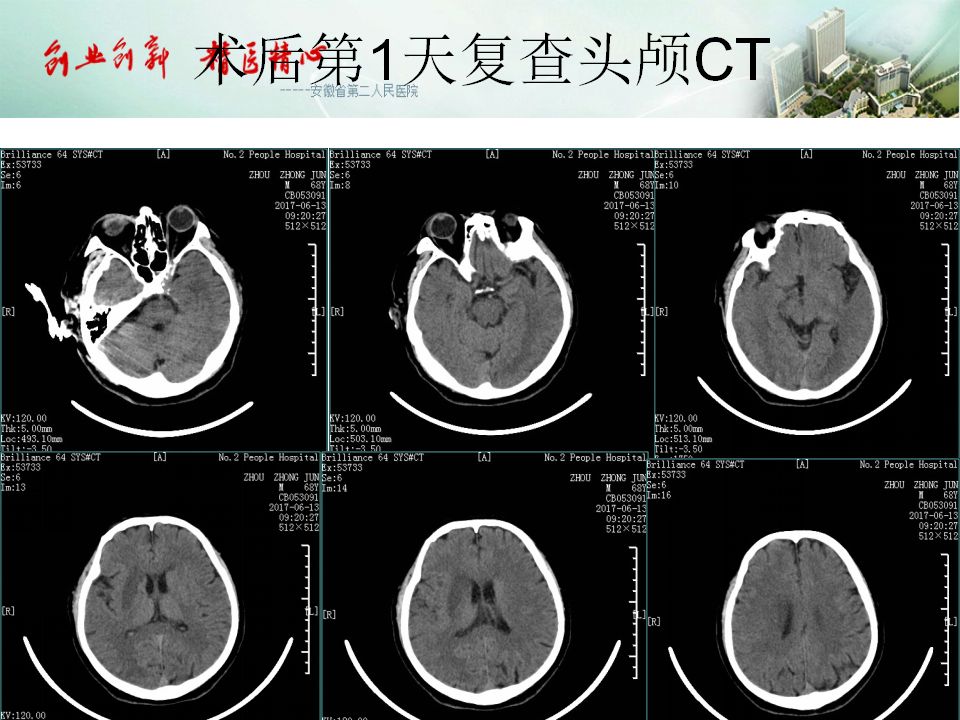

今天为大家分享的是“强生医疗CNV-神经介入专栏”第五十一期,由安徽省第二人民医院神经内科陈长春主任医师带来的“急性缺血性脑卒中超早期治疗--通与不通的哲学思考”精彩PPT,欢迎观看。文章仅代表作者个人观点,如有不同见解,欢迎同道斧正!